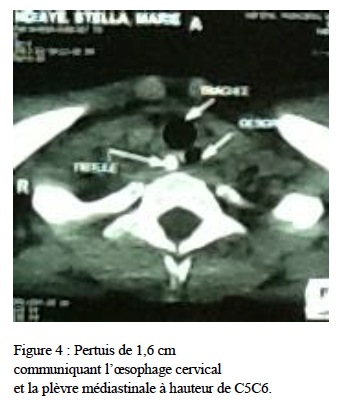

conforté par une deuxième tomodensitométrie avec reconstruction qui avait permis d’individualiser un pertuis de 1,6 cm communiquant l’oesophage cervical et la plèvre médiastinale à hauteur de C5C6 (figure 4).